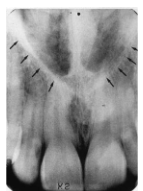

Incisive Foramen

small round radiolucent area between roots of max centrals

(radiolucent)

Superior Foramina of Incisive Canal

two tiny openings on the floor of the nasal cavity

Median Palatal Suture

thin radiolucent line between roots of max centrals

Nasal Cavity/Fossa

large radiolucent area above the max incisors (aka nasal fossa)

Nasal Septum

vertical radiopaque divider in the nasal cavity

(radiopaque)

Floor of Nasal Cavity

dense radiopaque band of bone above the max incisors

Anterior Nasal Spine

v-shaped radiopaque area at base of nasal septum

Inferior Nasal Conchae

diffuse radiopaque projection in the nasal cavity